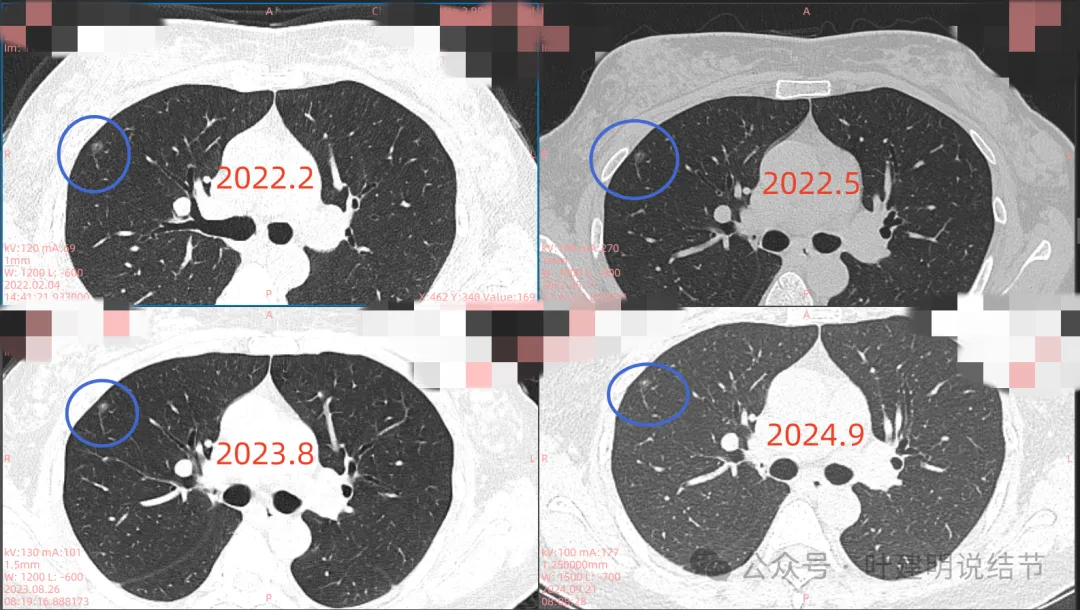

影像展示与分析:

我们先来看2022年2月时病灶最明显部位的截图:

这是A医院主张手术时的影像:

右上主病灶,磨玻璃密度,灶内不是很均匀,似见小空泡征,有微小血管走向病灶并进入,但说不上明显异常增粗,整体轮廓与边界清,考虑是肿瘤范畴的结节。

再看2022年5月时的影像:

这时B医院医生主张手术时的情况:

三处病灶均仍在,间隔3个月显然说不上明显进展或变化。这时候问诊我,我对比后认为风险仍低,能再随访,结友停掉了本已经预约的手术。

再看2023年8月时复查的影像:

有变化吗?说不上!

最后来看2024年9月,也就是叫停手术后2整年之后复查的情况:

仍说不上有明显进展,如果将这几次的放在一起来对照,就会更加直观:

病灶基本上没有明显变化。当然不必过于在意具体大小有没有几毫米的差别,也不必在意具体CT值有几十或百把的区别,微细的差别不影响临床决策,也就是说改变都不足以让肉眼发现的,怎么会影响预后呢!

我看了你2022年2月时的片子,以及某医院建议你手术说有进展时的2022年5月时的片子和2023年8月复查时的片子,再对比2024年9月时的影像,总体上明显点的病灶仍是这三处。首先均仍是纯磨,有的似有微血管进入或穿行,但磨玻璃成分密度很淡,而且大小无明显进展。至于右上病灶是否有缩小好转,感觉上右上的与右中叶的都略显淡了点,我怀疑还是扫描条件不一的关系,本身又是非常小而淡的病灶,可比性稍差,并不能说明必是有吸收好转。但肯定说不上有进展,风险仍是低的,半年或一年复查随访(个人倾向可以年度复查)总归不至于会耽误病情。意见供参考!